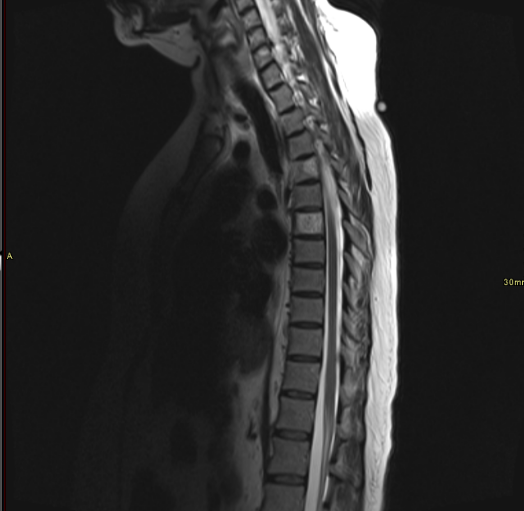

50 yr female was presented with neck and interscapular pain and was referred for MRI covering cervical spine and scapular region. On basis of findings on initial findings, patient was recalled for further MRI imaging.

What are the imaging findings and diagnosis?